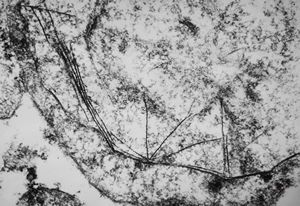

M,18y. | tubuloreticular complex in lymphocyte - unclassified hematologic disorder